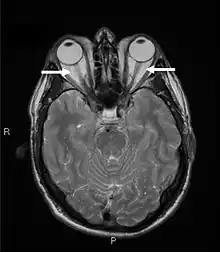

Orbital imaging is an integral tool for the diagnosis of Graves' ophthalmopathy and is useful in monitoring patients for progression of the disease. It is, however, not warranted when the diagnosis can be established clinically. Ultrasonography may detect early Graves' orbitopathy in patients without clinical orbital findings. It is less reliable than the CT scan and magnetic resonance imaging (MRI), however, to assess the extraocular muscle involvement at the orbital apex, which may lead to blindness. Thus, CT scan or MRI is necessary when optic nerve involvement is suspected. On neuroimaging, the most characteristic findings are thick extraocular muscles with tendon sparing, usually bilateral, and proptosis.